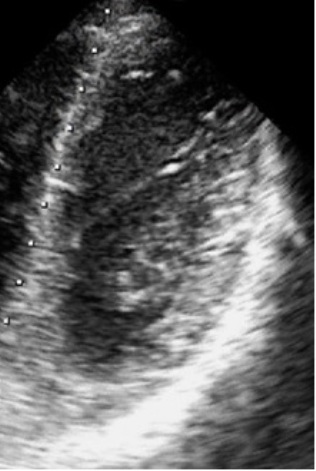

Группу исследования составили 90 здоровых молодых людей (48 девушек и 42 юноши) в возрасте 20,2±2,9 лет, активно занимающихся физической культурой и спортом. Наличие у испытуемых дисплазии соединительной ткани было подтверждено в соответствии с Национальными рекомендациями по диагностике и лечению наследственных нарушений соединительной ткани (2012). Было выполнено стандартное эхокардиографическое исследование с последующей цифровой обработкой видеоизображений сердца для построения 3D-модели ЛЖ и оценки региональной функции миокарда. Способность сердца адаптироваться к физическим нагрузкам была определена с помощью нагрузочного тестирования на тредмиле.

Описание топологи ЛС в рамках 3D-модели ЛЖ выявило наличие от 1 до 5 сухожилий на один ЛЖ, которые преимущественно были расположены в высоких отделах желудочка, и ориентированы перпендикулярно или под небольшим углом к его длинной оси. Основные показатели глобальной структуры и функции ЛЖ были в пределах нормы, однако у всех лиц была выявлена высокая степень механической асинхронности в покое. Также была обнаружена большая вариабельность значений показателей, характеризующих способность сердца адаптироваться к физическим нагрузкам. Методами корреляционного, однофакторного и многофакторного анализа данных установлено: чем больше ЛС на один ЛЖ, тем выше уровень исходной механической асинхронности и ниже способность сердца адаптироваться к физическим нагрузкам.